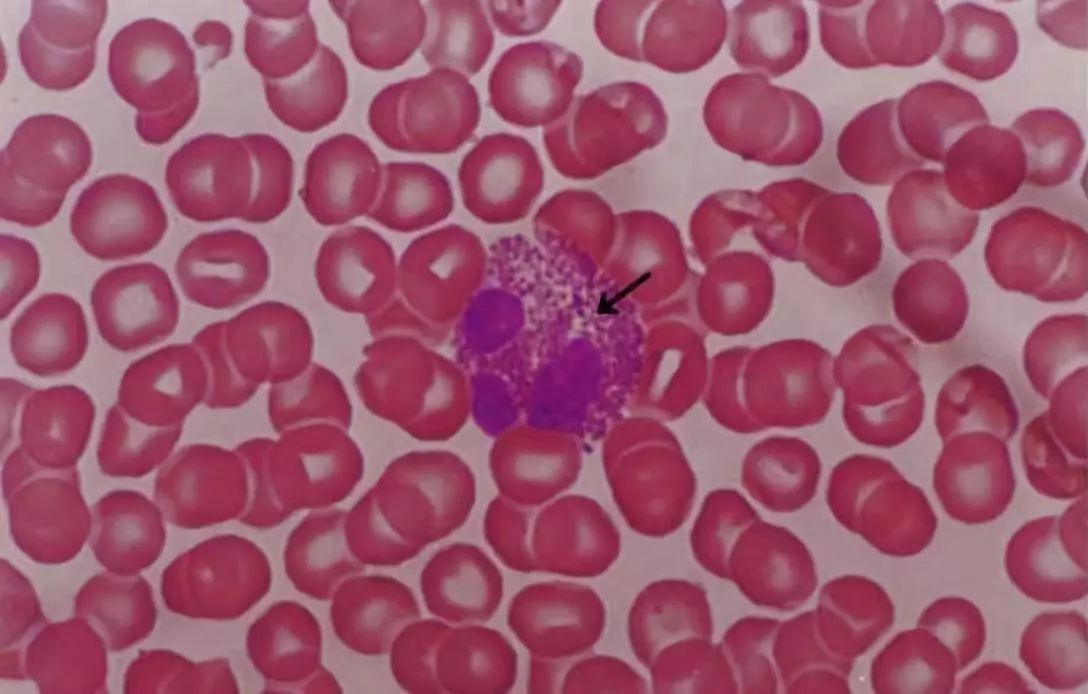

图3.血涂片光镜像(Wright 染色)

箭头指示的是单核细胞,球形细胞,直径14-20μm,核肾形、马蹄形或卵圆形,染色较浅,胞质丰富,染成灰蓝色。

图4. 血涂片光镜像(Wright 染色)

箭头指示的是嗜酸性粒细胞,球形细胞,直径10-15μm,分叶核,多为两叶,胞质内充满粗大的、分布均匀的、红色颗粒。